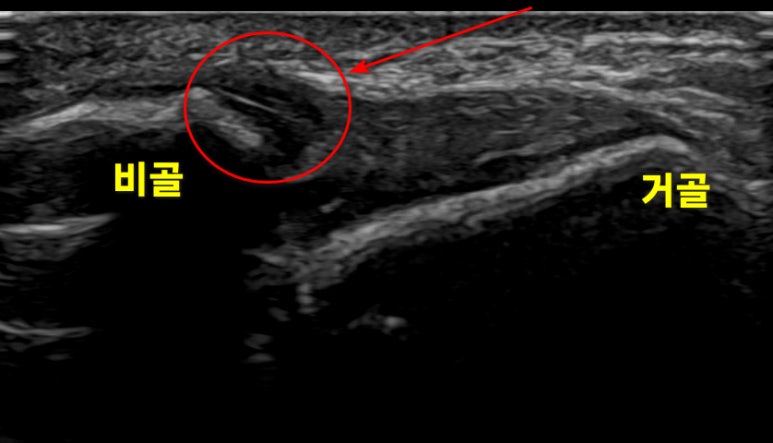

좌측 정상 구허혈, 우측 환자분의 구허혈

빨간 동그라미 표시에서

차이가 보이시나요?

현대 한의학은

통합의학이므로

전통적으로 해왔던 것처럼

손 끝 감각으로

병변이 있는 혈 자리를 찾은 뒤

MRI, 초음파 등

현대의료기기를 이용해서

문제가 되는 혈자리에

정확하게 치료합니다.

초음파 유도하 시술

조직 재생을 유도하기 위해

초음파 가이드 특수침을

시술했습니다.

실시간으로

니들 끝의 위치를 확인하며

문제가 있는 혈자리에

정밀하게 치료합니다.